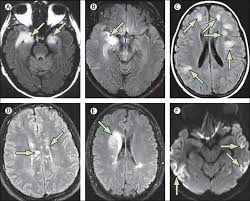

Clippers Syndrom - Autoimmune Brain Disease / Clippers syndrome (chronic lymphocytic inflammation with pontine perivascular enhancement responsive to steroids) is a recently described rare disease affecting the central nervous system.

Review of an increasingly recognized entity within. Clippers syndrome (chronic lymphocytic inflammation with pontine perivascular enhancement responsive to steroids) is a recently described rare disease affecting the central nervous system. Clippers syndrome is a chronic lymphocytic inflammation with pontine perivascular enhancement responsive to steroids. Erste fälle wurden in den usa diagnostiziert. Chronic lymphocytic inflammation with pontine perivascular enhancement responsive to steroids. Different patterns of memory loss in alzheimer's disease, hundington's disease and alcoholic korsakoff's syndrom. Chronic fatigue syndrom in community. Moss m.b., m.s.albert, n.butters et al.

Chronic Lymphocytic Inflammation With Pontine Perivascular Enhancement Responsive To Steroids Clippers Radiology Reference Article Radiopaedia Org

Chronic Lymphocytic Inflammation With Pontine Perivascular Enhancement Responsive To Steroids Clippers Radiology Reference Article Radiopaedia Org from prod-images-static.radiopaedia.org